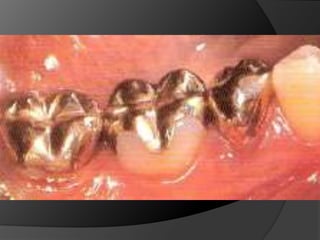

INLAY DE METAL: Restauraciones pequeñas o medianas con pocos requerimientos estéticos. El material de elección	 es el oro.  (OP – OMD)INLAY DE CERÁMICA: Estética y Adhesión a la estructura dentaria. (OP – OMD)

CORONA COMPLETA EN METAL: 	En dientes con múltiples superficies axiales defectuosas o destruidas. Proporciona la máxima retención.	La superficie oclusal	favorece  el chequeo oclusal